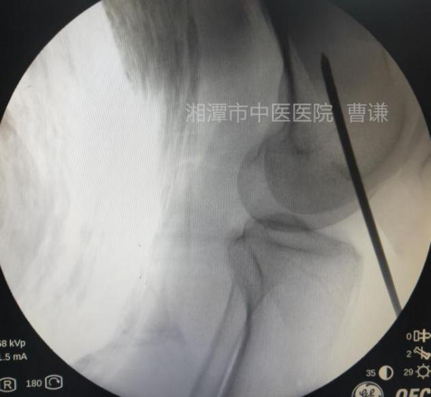

麻醉生效后,常规消毒铺无菌巾,先在体表放置一根克氏针透视,确定骨折端适宜钢丝捆扎的部位。

在透视确定的平面上,分别在大腿前方及稍偏后的外侧做约1.5cm小切口,用一把中号弯钳夹持丝线

(建议采用5号肌腱线或最粗可吸收线,不容易断,注意夹线时多折几折,这样另一把止血钳很容易夹住)。

自后外侧切口插入,触碰到骨干后向下滑走,沿骨干后方贴骨膜外伸至断端内侧。

用另一把中号弯钳自前方小切口进入,抵达骨面后沿股骨内侧向后伸至股骨后内侧。

此时可以触碰到第一把中号弯钳,当第二把弯钳的尖端感受到第一把弯钳的尖端,尝试张口钳夹并向上提拉,感受到第一把弯钳随之而动,说明已钳夹到导引线。

继续提拉第二把弯钳直至导引线从前方切口拉出。

透视见钢丝逐渐拧紧并使骨折端靠近复位。